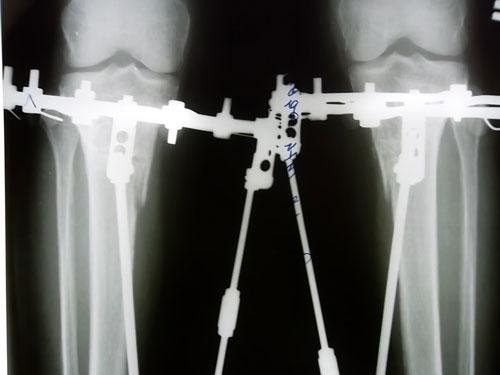

Дата операции 14.08.2012г.

Дата снятия аппаратов 15.11.2012г.

Срок лечения 90 дней.

В аппаратах в день снятия.